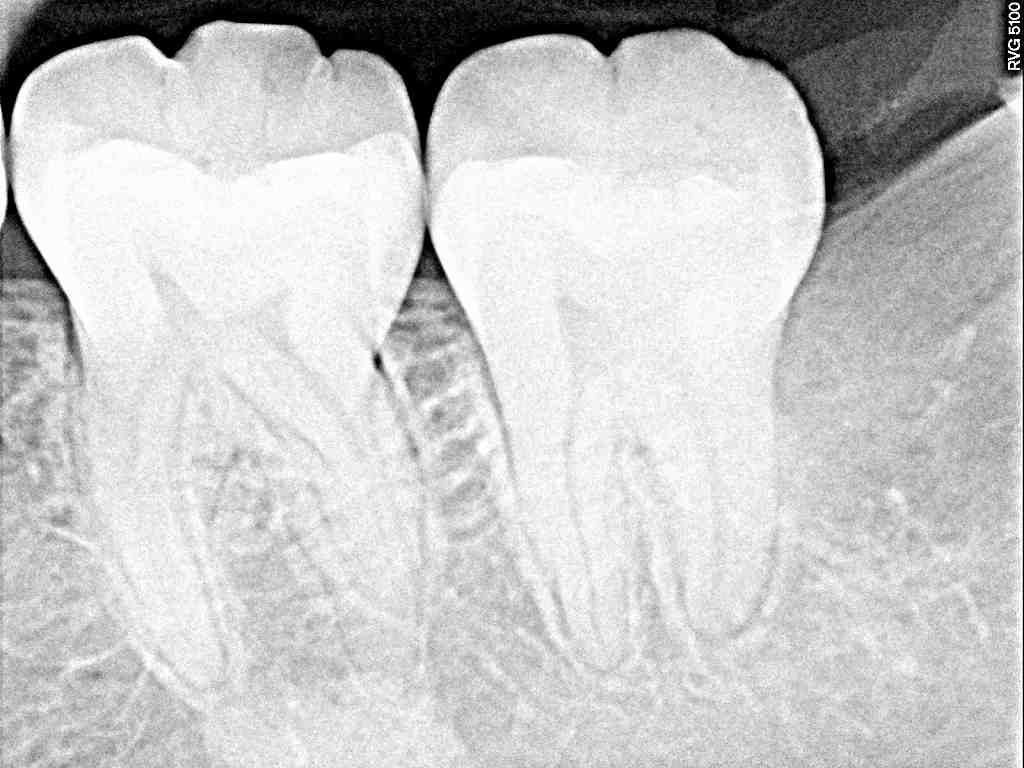

左下の奥の見えていない親不知の難抜歯 水平埋伏歯の難抜歯|お知らせ |広島市安佐南区の歯科医院 左下の奥の見えていない親不知の難抜歯 水平埋伏歯の難抜歯 トップ お知らせ・ブログ お知らせ 左下の奥の見えていない親不知の難抜歯 水平埋伏歯の難抜歯 左下の奥の見えていない親不知の難抜歯 水平埋伏歯の難抜歯 術前のパノラマになります 全く見えていません 遠心部のここに埋まっています 最小限で開けていきます 歯冠部を分割抜歯していきました 根部を取り出していきました 縫合して終了となります 歯牙を取り出していきました 綺麗に除去していきました Web診療予約 初めての方へ 選ばれ続ける理由 院内設備について 歯が痛いしみる一般歯科 歯がぐらぐらする歯周病 健康な歯を保ちたい予防歯科 子供の虫歯予防をしたい小児歯科 銀歯をセラミックに審美歯科 白い歯を目指しませんか?ホワイトニング 矯正専門医がいるので安心矯正歯科 抜けた歯を補いたいインプラント・入れ歯 医院案内 スタッフ紹介 メリィハウス歯科クリニックオフィシャルホームページ ラベンダー歯科クリニックオフィシャルホームページ お知らせ・ブログ ホーム 診療科目 一般歯科 歯周病治療 予防治療 小児歯科 審美治療 ホワイトニング 矯正歯科 入れ歯・インプラント マウスピース矯正 初めての方へ 院長・スタッフ 設備紹介 医院案内・アクセス メニューを閉じる